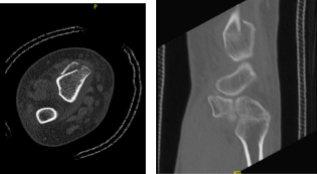

The patient presented results for CT scan that showed acute-to-subacute intra-articular fracture of the right distal radius as detailed above. Companion fracture of the ulnar styloid as noted. Small joint effusions. Chondrocalcinosis as detailed above.

CT Right wrist non-contrast